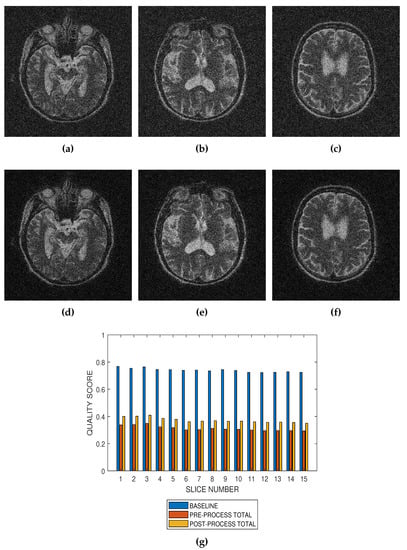

Performance of the noise reduction algorithm at 4 percent, 8 percent and 12 percent noise levels are displayed in Figure 7, Figure 8 and Figure 9, respectively. In the three levels of Rician noise, the post processing quality scores are higher than corresponding preprocessing quality scores.

Figure 9.

Application of the proposed method to the assessment of an image enhancement algorithm. (a–c) are slices numbers 20, 27 and 34, respectively in a T2 MRI volume degraded with 12 percent Rician noise. (d–f) are the slices displayed in (a–c) but their quality have been enhanced using a bilateral filter. (g) The baseline quality score of the original image, the predicted total quality indices of 12 successive T2 MRI slices in a volume data before and after enhancement with a bilateral filter.

Performance evaluation of noise reduction algorithms will be a useful application of the proposed method. Evaluation of the proposed methods before and after denoising MRI images (See Figure 7, Figure 8 and Figure 9) show that the performance of noise reduction algorithms decreases with the severity of noise.